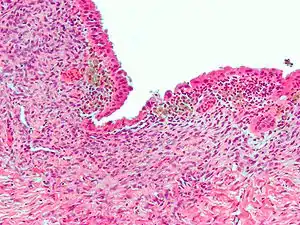

| عکاسی ریزنگاری آندومتریوز (H&E stain)، علت رایج درد مزمن لگنی در زنان را نشان میدهد. |

آندومتریوز

وجود بافت غدد یا استرومای رحم، در محلی غیر از رحم که شایعترین جا حفره لگن است و عوارضی برای فرد مبتلا به همراه دارد.

بین وسعت آندومتریوز و میزان دردی که ایجاد میکنند ارتباط مستقیمی وجود ندارد و دیده شده هرچه وسعت آندومتریوز کمتر باشد درد بیمار بیشتر است.

درد ناشی از آندومتریوز میتواند پیش از قاعدگی، در حین قاعدگی یا حتی پس از آن ادامه یابد.

تشخیص قطعی آندومتریوز با لاپاراسکوپی و نمونه برداری از نقاط آندومتریوز و تأیید پاتولوژی بافت است.